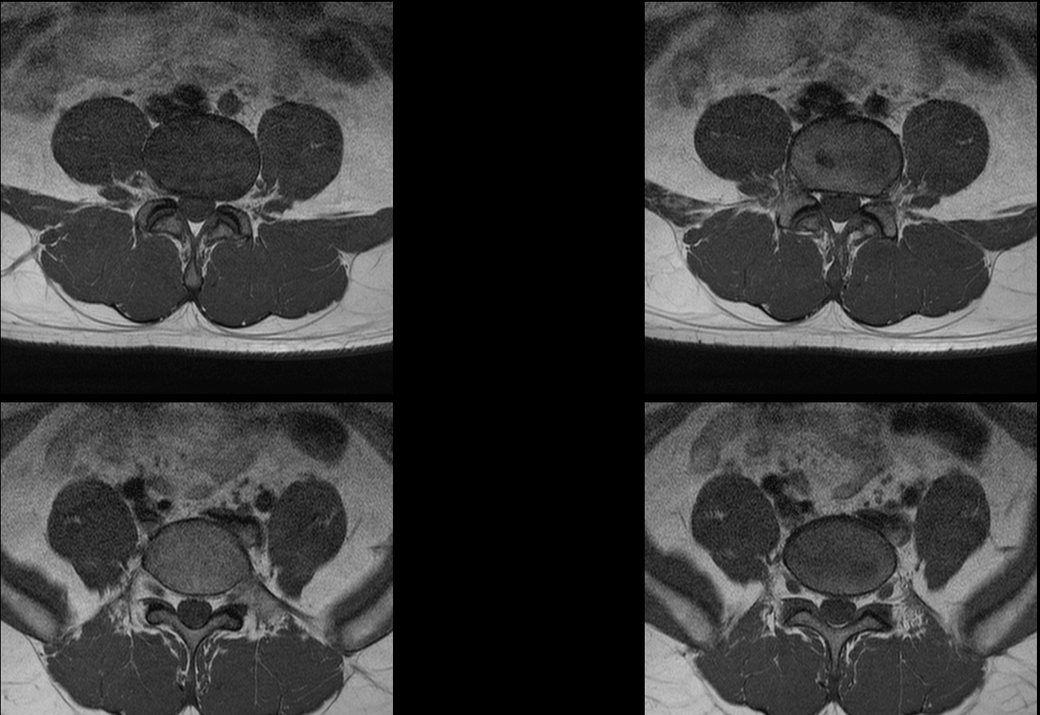

MRI 판독지 및 사진 해석 부탁드립니다.

1년전에 허리가 안좋아서 MRI를 찍었는데 저번주에 경미한 교통사고가 났습니다.

그 후 다리에 저림증상이 있기 시작했고 피가 안통하는 느낌이 들기 시작했습니다.

경미한 교통사고가 다리저림에 원인일 수 있을까요? MRI판독 부탁드립니다 ㅠㅠ

현재

• 3번 째 사진

1년 전 사진에 비해 허리디스크 상황이 악화된 것으로 생각됩니다. 다리저림은 이로 인한 증상으로 생각됩니다.

그러나, 말씀하신 내용과 검사결과만으로는 교통사고와의 연관성에 대해 단정지어 말하기는 어렵습니다. 증상이 점차 악화되어 발생한 것인지, 교통사고에 의해 갑자기 악화된 것인지에 대한 판단이 추가로 필요하겠습니다.